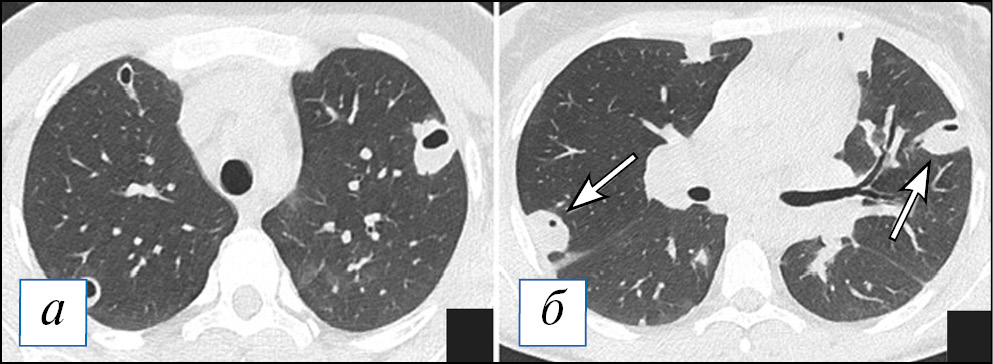

По данным компьютерной томографии (КТ) у пациентов с очаговой пневмонией обнаруживают небольшие перибронхиальные очаги, обычно солидного типа или с нечеткими контурами за счет ободка «матового стекла», при бронхиолите — мелкие очажки в виде симптома «дерева с набухшими почками», при этом прилежащие стенки бронхов могут быть утолщены и уплотнены за счет воспалительного процесса. Возможно слияние очагов, которое не принимает характера обширной инфильтрации. При пневмонии контуры очагов менее четкие из-за преобладания экссудативного воспалительного компонента, что отличает ее от бронхиолита [38]. Важным симптомом бронхогенного процесса можно рассматривать наличие патологического содержимого в просвете бронхов, что представлено слизистым или гнойным содержимым (рис. 1). На традиционных рентгенограммах изменения из-за малого размера могут быть вовсе не заметны или представлять собой мелкие очаги/ограниченную диссеминацию; отмечается локальное усиление/обогащение легочного рисунка, преобладающее в какой-то одной доли легкого.

Рис. 1. Компьютерная томография органов грудной клетки в аксиальной проекции (а–г). Двусторонняя сливная бронхопневмония и бронхиолит у пациента с наличием в мокроте S. pneumoniae и S. aureus в значимых титрах. С обеих сторон, больше в нижних долях, на фоне обтурации просветов крупных бронхов патологическим содержимым (стрелки) имеются перибронхиальные разнокалиберные очаги, в том числе по типу симптома «дерева с набухшими почками» (рамка). В верхних отделах данные очаги сливаются в инфильтраты. [Изображения из архива авторов]. / Fig. 1. Chest CT, axial projection (а–г). Bilateral bronchopneumonia and bronchiolitis (with the etiology of S. pneumoniae and S. aureus confirmed by a sputum test). On both sides, more in the lower lobes against the background of bronchial sputum obturation (arrows), there are peribronchial nodules of various sizes, including a “tree in bud” sign (frame). In the upper lungs areas the nodules formed infiltrates. [Images from the authors’ archive].